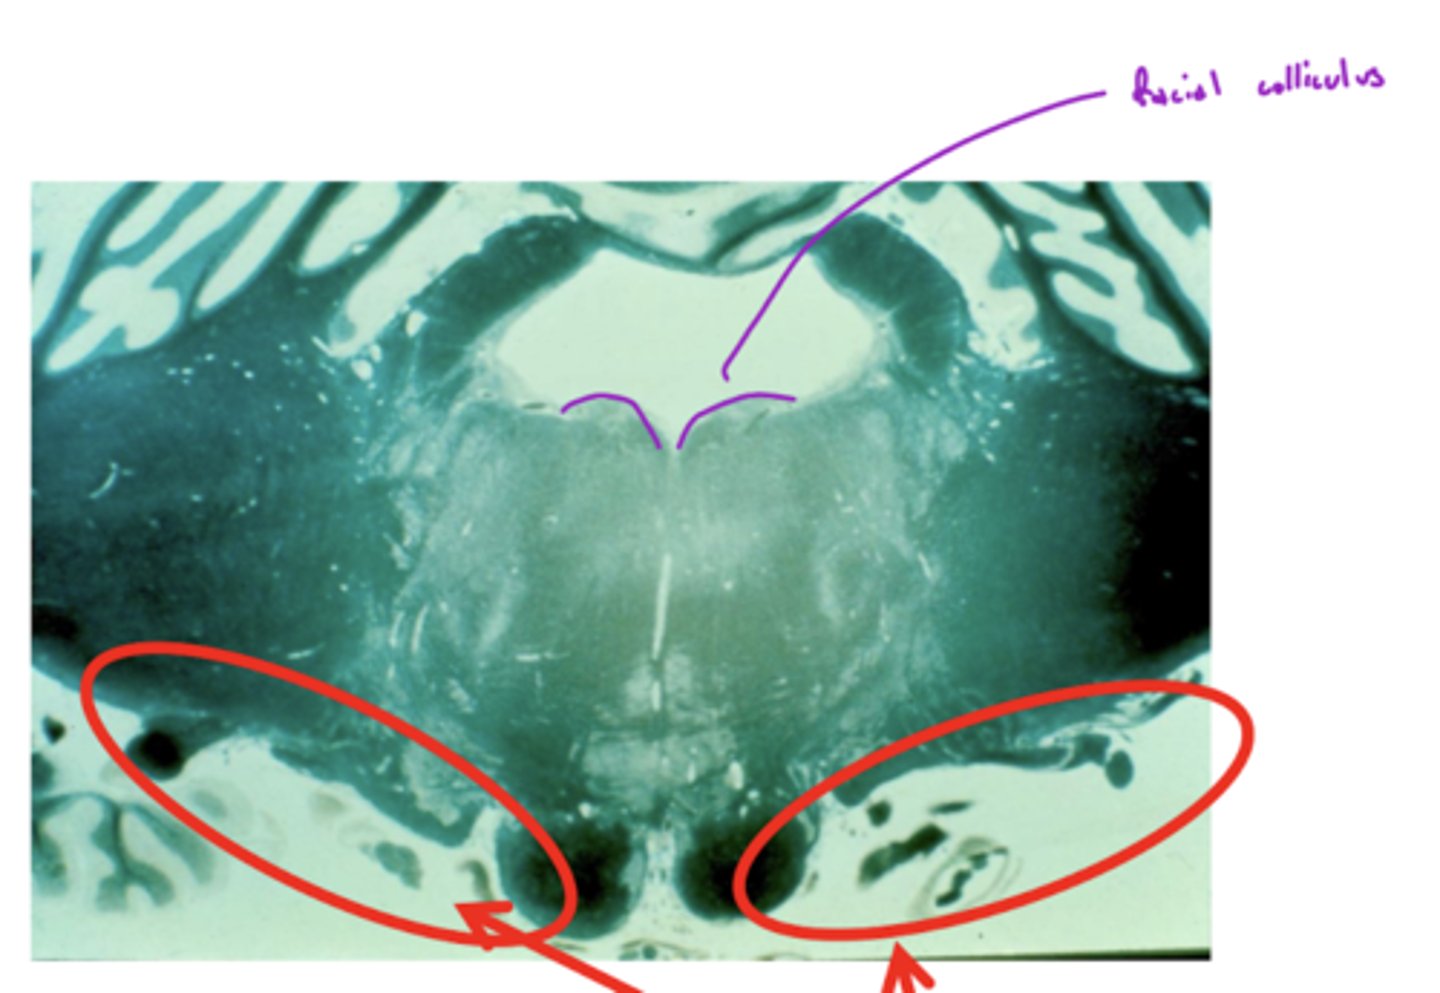

What nuclei are at the pontomedullary junction?

1. SVE of CN VI

2. SVE of CN VII (facial)

What are the facial colliculi?

bumps (hills) coming out from dorsal pontomedullary junction into the 4th ventricle -- CN VII SVE fibers create this space when they wrap around the abducens nucleus

Where do CN VI, VII, VIII exit the pons?

pontomedullary junction

What is the spacing of CN VI, VII, and VIII exiting the pontomedullary junction?

8 & 7 -- lateral and closer together

6 -- medial and far away

image -- look at red font